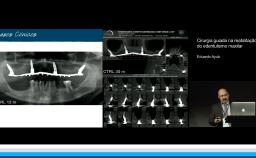

Como tornar a cirurgia mais simples e previsível

A apresentação demonstra fatores de risco relacionado ao resultado protético com implantes. Ressalta as expectativas dos pacientes no tratamento e como planejar procedimentos cirúrgicos de forma a se aproximar destas expectativas. Para isso, são destacados a importância do conhecimento da anatomia do rebordo alveolar, e como seus defeitos de tecidos duros e moles impactam a morfologia dos tecidos perimplantares. Também, são discutidos estratégias para obtenção de estabilidade através de técnica cirúrgica, conhecimento da macrogeometria e tecnologia de superfície. Além disso, a relevância da  posição ideal para estabilidade tecidual, e como o planejamento virtual e guias cirúrgicas podem auxiliar na obtenção da posição 3D são esclarecidas. Por fim, são descritos também o papel do volume de tecidos duros e as possíveis complicacões relacionadas a erros de planejamento.